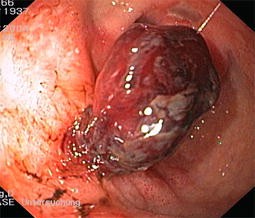

Abb. 3